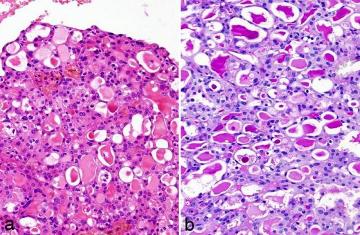

Sekreční karcinom slinných žláz mamárního typu (MASC) je nově popsaný karcinom slinných žláz, častější u žen, s afinitou k parotis, ale vyskytující se i v malých slinných žlázách dutiny ustní a v submandibulární žláze. Histologicky je MASC low grade karcinom, tvořený solidně mikrocystickými strukturami s typickou abundánní homogenní sekreční aktivitou (obr. 1).

Obr. 1. Histologická struktura sekrečního karcinomu mamárního typu (MASC)